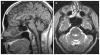

PNPLA6 mutations, known to be associated with the development of motor neuron phenotypes, have recently been identified in families with Boucher-Neuhäuser syndrome VSports手机版. Boucher-Neuhäuser is a rare autosomal recessive syndrome characterized by the co-occurrence of cerebellar ataxia, hypogonadotropic hypogonadism, and chorioretinal dystrophy. Gait ataxia in Boucher-Neuhäuser usually manifests before early adulthood, although onset in the third or fourth decade has also been reported. However, given the recent identification of PNPLA6 mutations as the cause of this condition, the determining factors of age of symptom onset still need to be established. Here, we have identified a sporadic Boucher-Neuhäuser case with late-onset gait ataxia and relatively milder retinal changes due to compound heterozygous PNPLA6 mutations. Compound heterozygosity was confirmed by cloning and sequencing the patient's genomic DNA from coding exons 26-29. Furthermore, both mutations (one novel and one known) fell in the phospholipase esterase domain, where most pathogenic mutations seem to cluster. Taken together, we herein confirm PNPLA6 mutations as the leading cause of Boucher-Neuhäuser syndrome and suggest inquiring about a history of hypogonadism or visual changes in patients presenting with late-onset gait ataxia. We also advocate for neuroophthalmologic evaluation in suspected cases. .